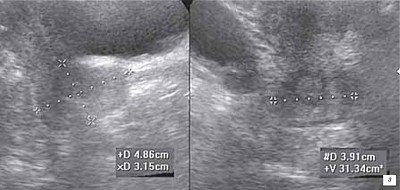

а) Рак шейки матки II стадии, неоднородная, увеличенная в объеме шейка.

б) Однородная изоэхогенная шейка матки нормальных размеров.

По данным УЗ-мониторинга после регионарной внутриартериальной химиоэмболизации, произведенной в качестве первого этапа химиолучевого лечения, у пациенток был отмечен значительный регресс опухоли шейки матки - уменьшение ее объема в среднем на 50% от первоначального (рис. 1, 2). Существенное уменьшение количества визуализируемых внутриопухолевых сосудов в ответ на СЛТ констатировано у 16 (64%) больных. Общий процент уменьшения объем шейки матки после курса СЛТ более 50% отмечен у 15 (60%) больных, менее 50% у 8 (32%), у 2 (8%) на фоне проводимого лечения наблюдалась отрицательная динамика. В процессе и после окончания курса СЛТ определялось уменьшение степени инфильтративных изменений. Структура опухоли визуализировалась как неоднородная с наличием множественных гиперэхогенных включений линейной формы или участка повышенной эхогенности, так называемой зоны "инициального" фиброза. При оценке васкуляризации определялось уменьшение количества визуализируемых сосудов опухолевого очага вплоть до полного их исчезновения. У большинства больных уменьшение объема опухоли в процессе комбинированного химиолучевого лечения происходило параллельно и пропорционально снижению степени ее васкуляризации. В 1 случае при наличии гиперваскуляризированной опухоли возникла необходимость проведения повторной внутриартериальной химиоэмболизации в конце лечения. В другом наблюдении повторная внутриартериальная химиоэмболизация подвздошных артерий у больной была выполнена при рецидиве заболевания и наличии опухоли в культе матки.